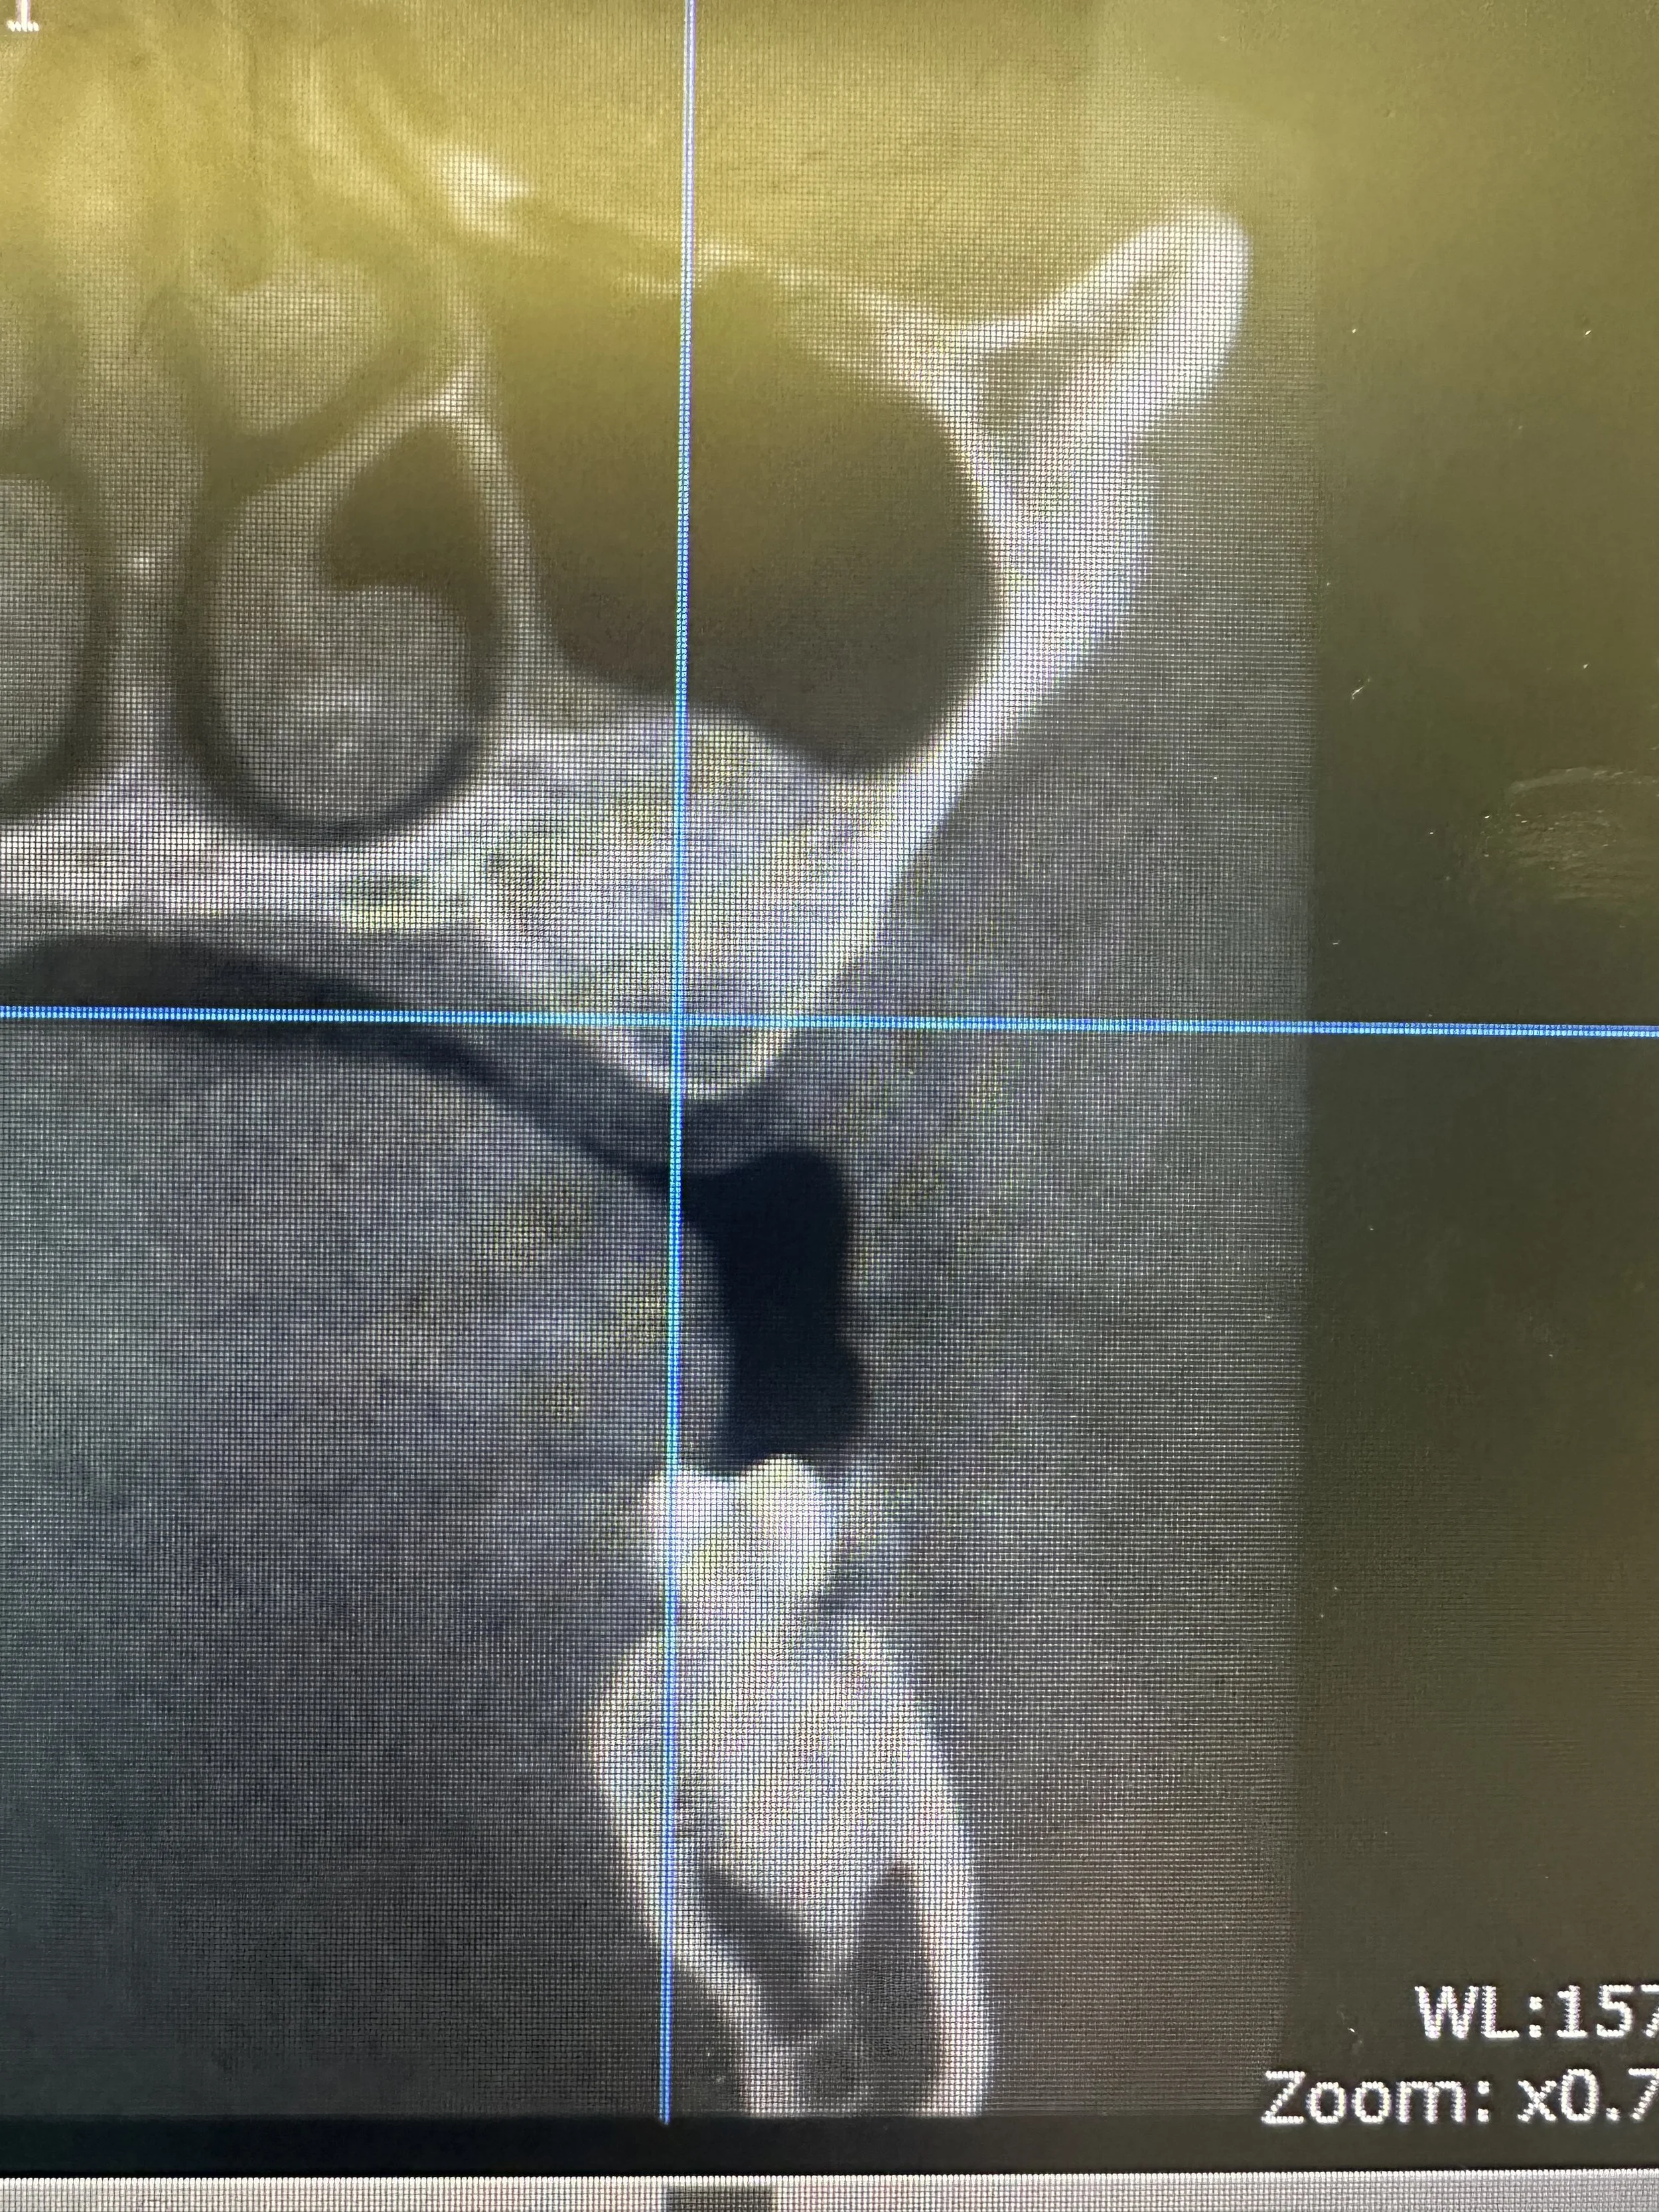

In this case, the patient presented with reduced vertical bone height in the upper left posterior region, making implant placement at site #14 unsuitable without prior augmentation. Advanced imaging confirmed the proximity of the maxillary sinus and the need for a staged surgical approach.

To restore the foundation for implant placement, a left maxillary lateral window sinus lift was performed. This technique allowed for controlled elevation of the sinus membrane and precise placement of bone graft material, increasing available bone volume while preserving surrounding anatomy.

Following adequate healing and bone maturation, implant placement at site #14 was completed with improved structural support and optimal positioning. Post-operative imaging demonstrated successful bone regeneration and stable integration of the implant within the augmented site.